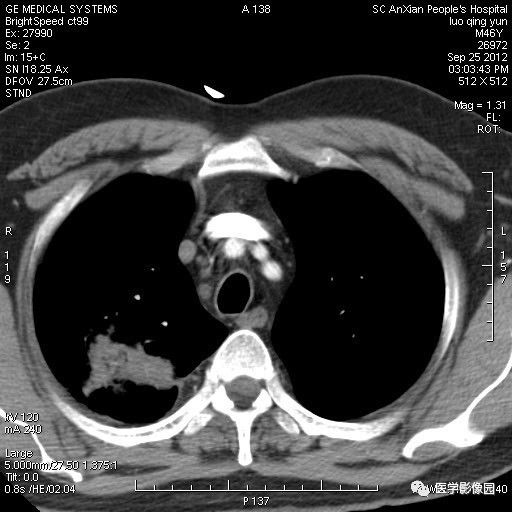

影像学表现:右上肺见不规则团块状高密度阴影,略有分叶级毛刺,边缘模糊,邻近胸膜增厚,增强扫描呈轻中度强化。

诊断结果:右上肺炎性假瘤

本病影像学表现无绝对特征性。单发多见,多位于肺表浅部位,多呈圆形或椭圆形,直径多在2-5cm或更大;多有假包膜,边缘多清晰光整,有时也毛糙,并可有分叶或毛刺;邻近胸膜局限性增厚、牵拉,病灶边缘呈桃尖样突起即桃尖征(尖端指向胸膜);增强扫描多呈中度均匀强化,持续时间较长。亦可显著强化。